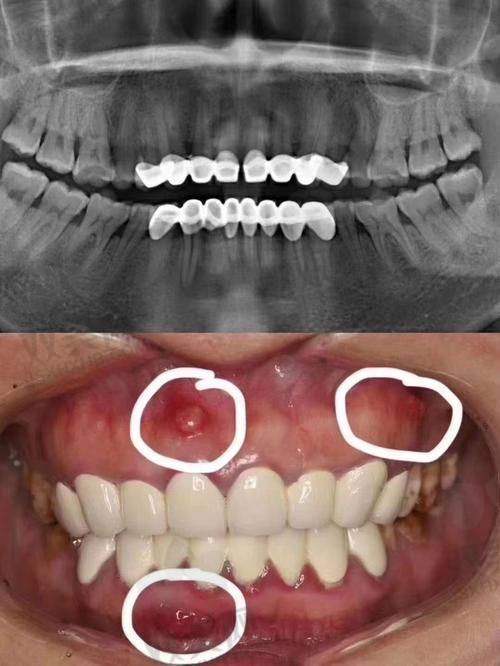

北京劲松口腔医院(蓝港分院)擅长多种口腔项目,包括牙齿矫正、牙齿种植、牙齿美白、口腔综合治疗等。在牙齿矫正方面,医院采用了多种精良的矫正技术,如隐形矫正、金属托槽矫正等,能够根据患者的牙齿情况和个人需求,选择更适合的矫正方案。牙齿种植是医院的另一大特色项目,医生们拥有丰富的种植经验,能够熟练运用各种种植系统,为患者提供稳定、美观的种植修复成效。牙齿美白项目则采用了精良的美白技术和材料,能够快速、安心地改善牙齿的色泽,让患者拥有洁白亮丽的牙齿。口腔综合治疗包括补牙、拔牙、根管治疗等,医院能够为患者提供全方面、专精的口腔疾病治疗服务。

北京劲松口腔医院(蓝港分院)的技术特点十分显著。首先,医院引进了国内外精良的口腔诊疗设备,如口腔CT、数字化牙片机等。这些设备能够为医生提供正确的诊断依据,提高治疗的精细度。其次,医院采用了精良的口腔治疗技术,如微创拔牙技术、微痛根管治疗技术等,能够减少患者在治疗过程中的痛苦。此外,医院还注重技术的创新和发展,不断引进新的技术和理念,为患者提供更加优质、效率高的口腔治疗服务。